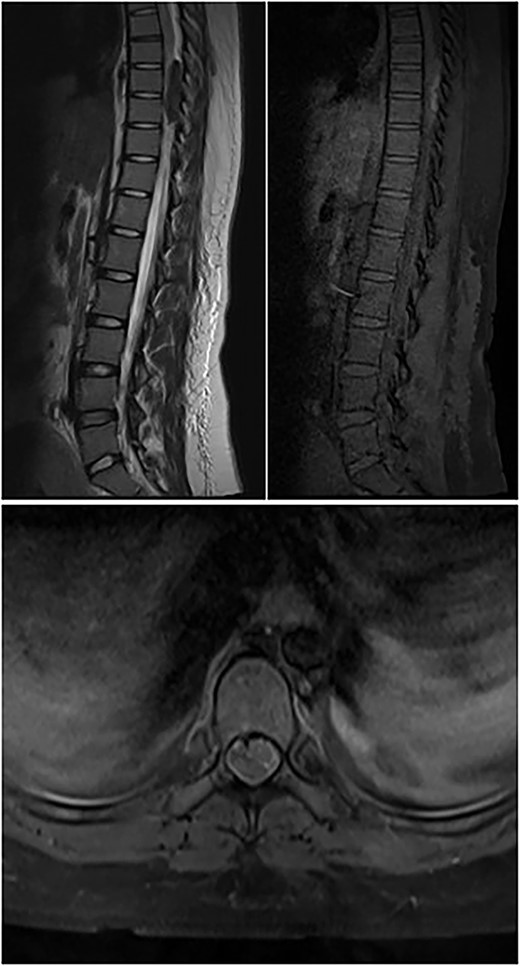

A 31-year-old post-partum female presented with acute onset paraparesis on the third day following uneventful caesarean delivery under combined spinal epidural anaesthesia. The patient was referred to our hospital 1 week after delivery with Grade 2 power in left lower limb and Grade 3+ power in right lower limb. There was graded sensory loss below D12 level. Lower limb deep tendon reflexes were exaggerated and bilateral plantar reflexes were extensor. Bladder and bowel were not involved. MAS Grade 1 spasticity was seen in bilateral lower limbs. MRI revealed an ovoid solid lesion behind the D11 vertebral body, which was hypointense in T1W and hyperintense on T2W images (Fig. 1). The following day, she underwent a dorsal laminectomy (D10–11) and the excision of the tumour without any instrumentation. The patient recovered uneventfully from the surgery and had rapid improvement in lower limb muscle strength. On discharge, the patient was independently ambulatory and had Grade 4/5 power in bilateral lower limb. She had improvement in sensation following surgery. On 3-month follow-up, the patient had full motor recovery and was able to walk independently. A repeat MRI showed no residual tumour.

Preop sagittal T2W image showing hyperintense SOL consistent with schwannoma.